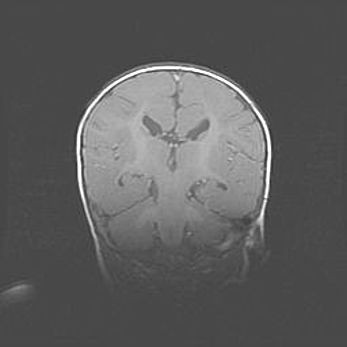

Наружная гидроцефалия с возможной атрофией височных областей.

Возраст: 28 дней

Вес: 3670 г

Пол: мужской

Окружность головы: 38 см

Срок гестации: 40 недель

Гидроцефалия головного мозга у новорожденных – это заболевание, которое характеризуется скоплением избыточного количества спинномозговой жидкости в желудочковой системе головного мозга в результате затруднения её перемещения от места выработки к месту поглощения в кровеносную систему или вследствие нарушения абсорбции. При открытой наружной форме гидроцефалии у новорожденных расширяются и переполняются субарахноидные пространства.

При нормотензивных  формах,  которые,  как  правило,  являются  следствием  перенесенных ишемических  повреждений  паренхимы  мозга,  возможно  сочетание микроцефалии  с нормотензивной гидроцефалией. В основе данных изменений лежит атрофия больших полушарий с преимущественной  локализацией  в  лобно-височных  областях.